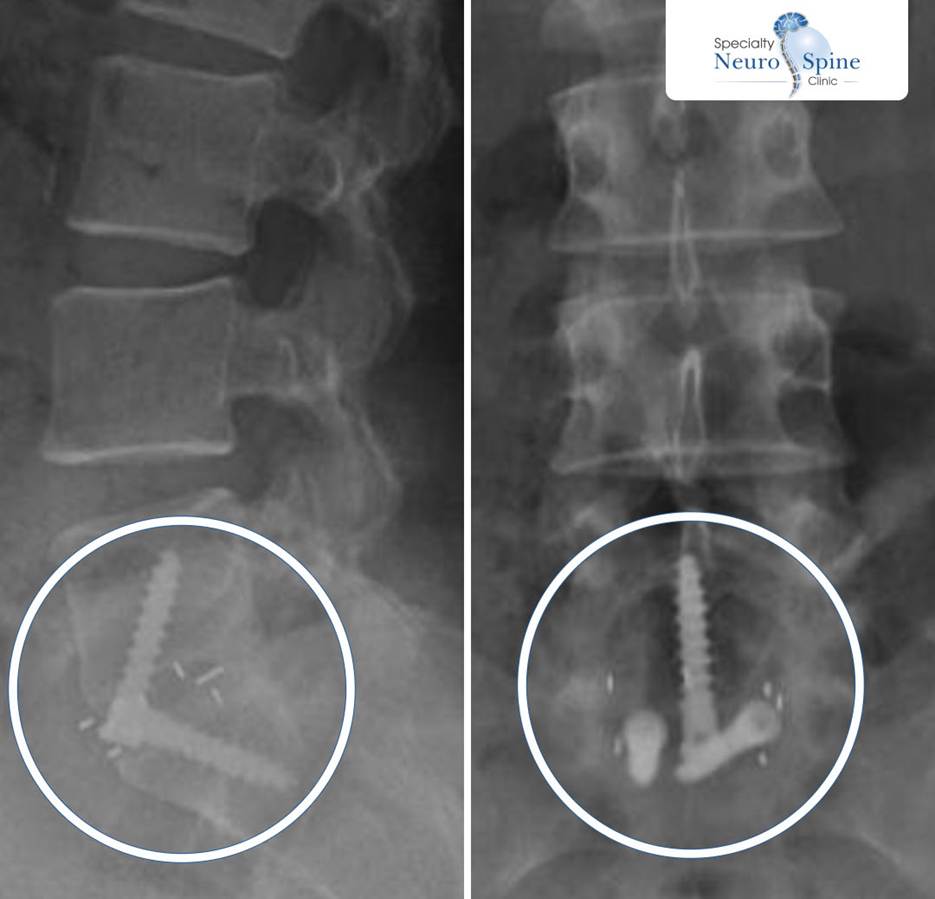

Perhaps the most compelling case treated by Dr. Firas Husban is Zainab’s, having undergone spinal fusion from L5 to S1 vertebras, using the OLIF technique with bone cage and anterior fixation.

The above X-Ray image shows the complexity of the OLIF procedure conducted by Dr. Firas Husban on Zainab more than 10 years ago – (Source: Dr. Firas Husban / Checkers Inc.)

One of the most intricate and composite procedures, Zainab’s post-operative imaging at the time (above) shows clear vertebral alignment and stability achieved through minimal intervention.

Today, a full decade later, Zainab continues to enjoy good health with a stable spine – living proof that OLIF delivers not just immediate relief, but lasting results.